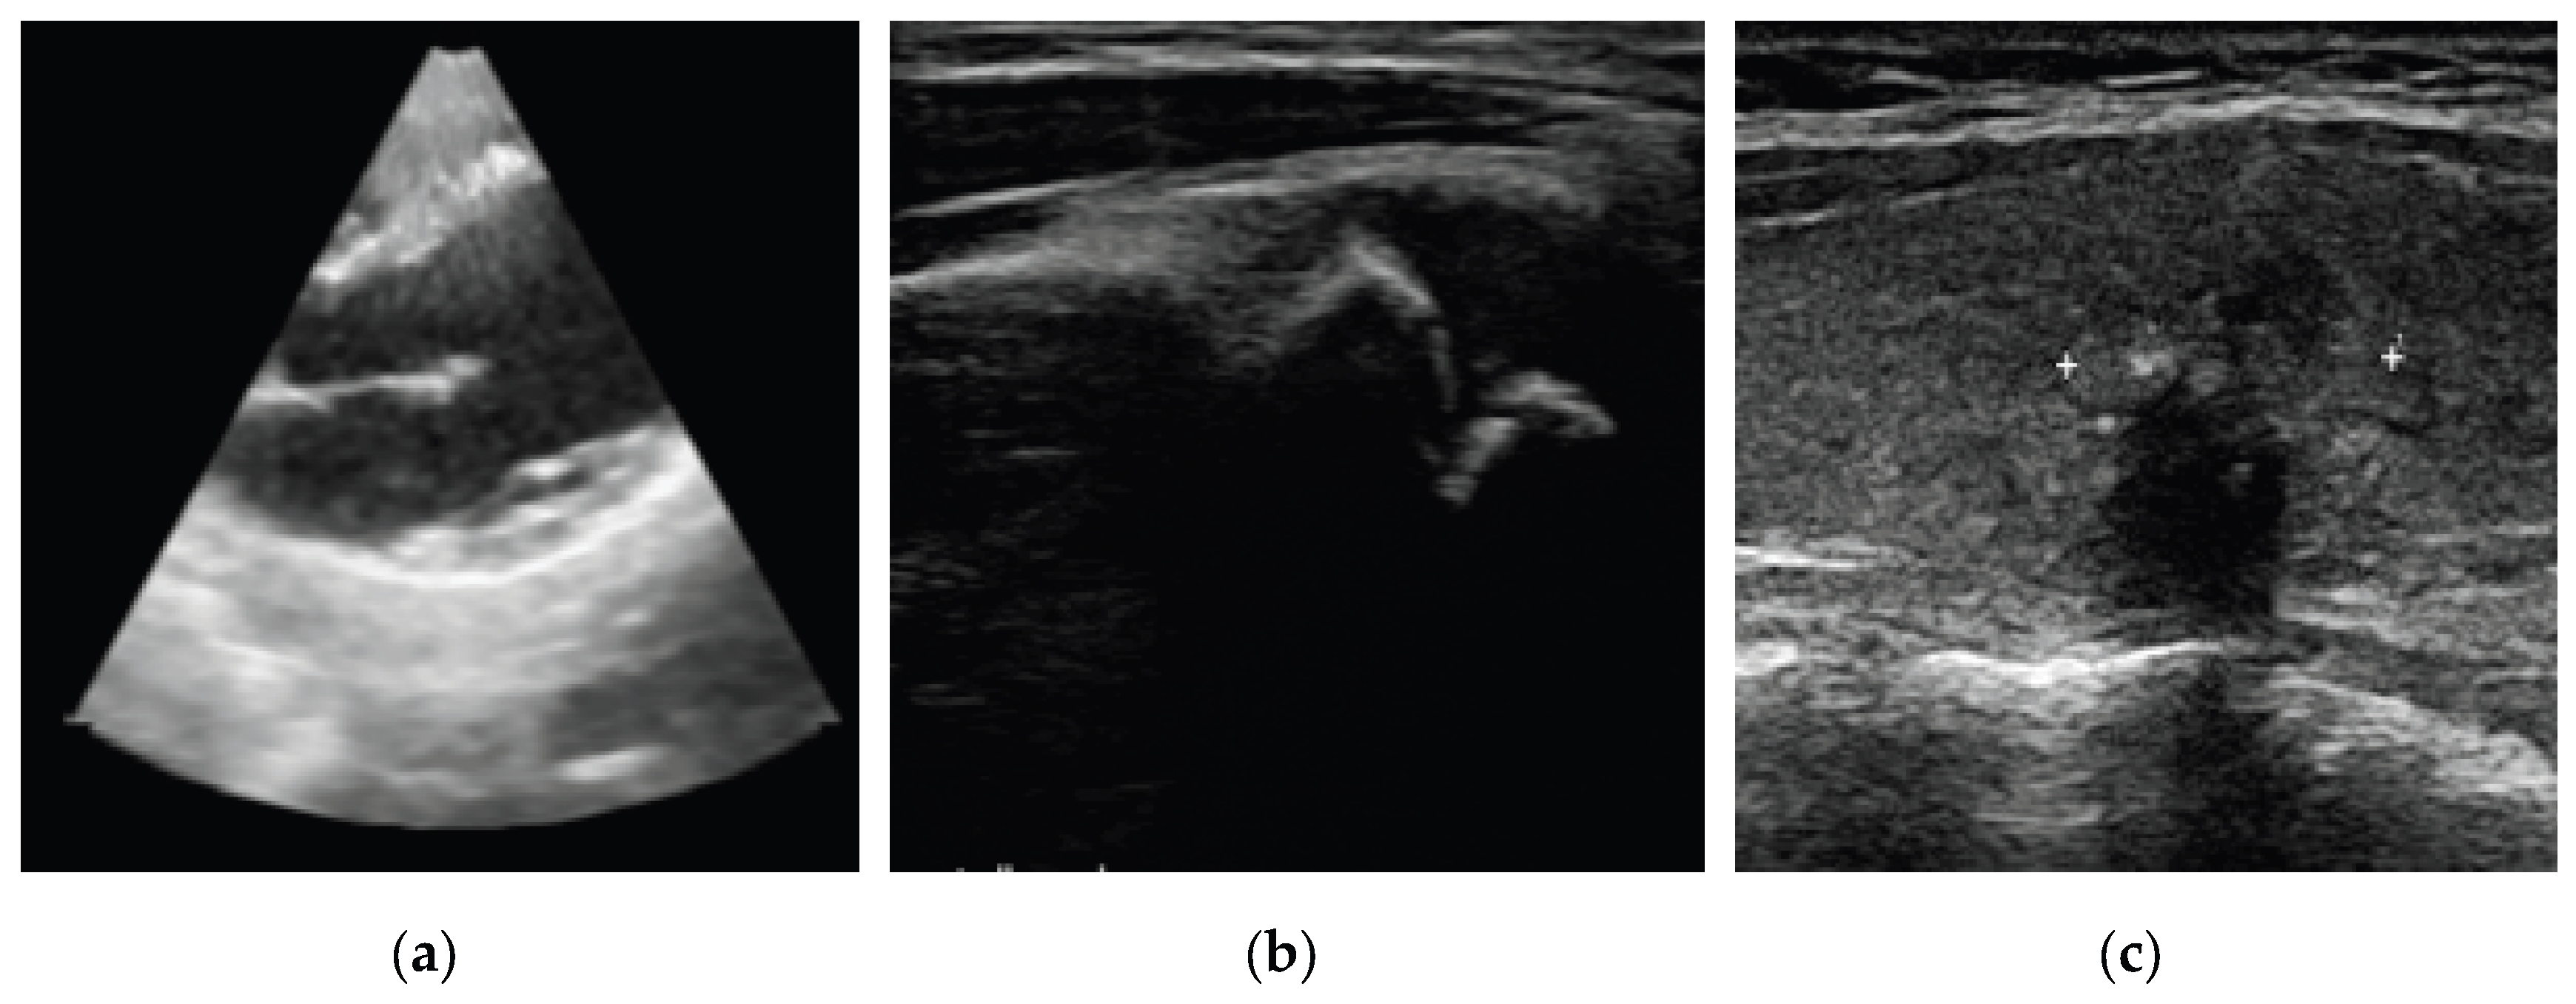

- Anatomy (Breast/ Fetal/ Cardiac/ Abdominal/Musculoskeletal/Others);